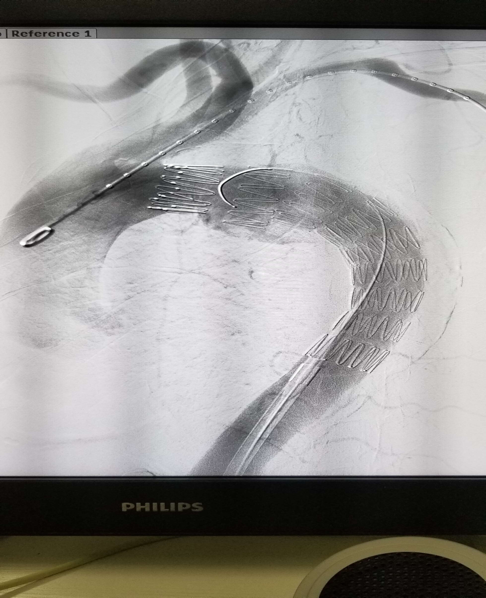

支架植入术后造影:

男,65岁,主动脉夹层(Stanford B型/Debakey III型),降主动脉和腹主动脉全程受累(见CTA箭头处),急诊行主动脉覆膜支架植入术,支架植入术后夹层消失,手术十分顺利。